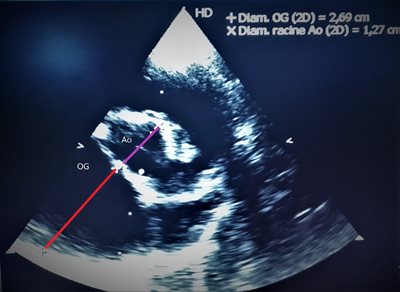

Il a été prouvé que lors de maladie valvulaire mitrale, seulement 50% des animaux atteint nécessiteront un traitement un jour. Pour déterminer cette nécessité médicale, le diagnostic le plus précoce passe par l’échocardiographie avec mesure entre autres du rapport oreillette gauche sur aorte. Sur cette image, l’animal nécessite la mise en place d’un traitement.